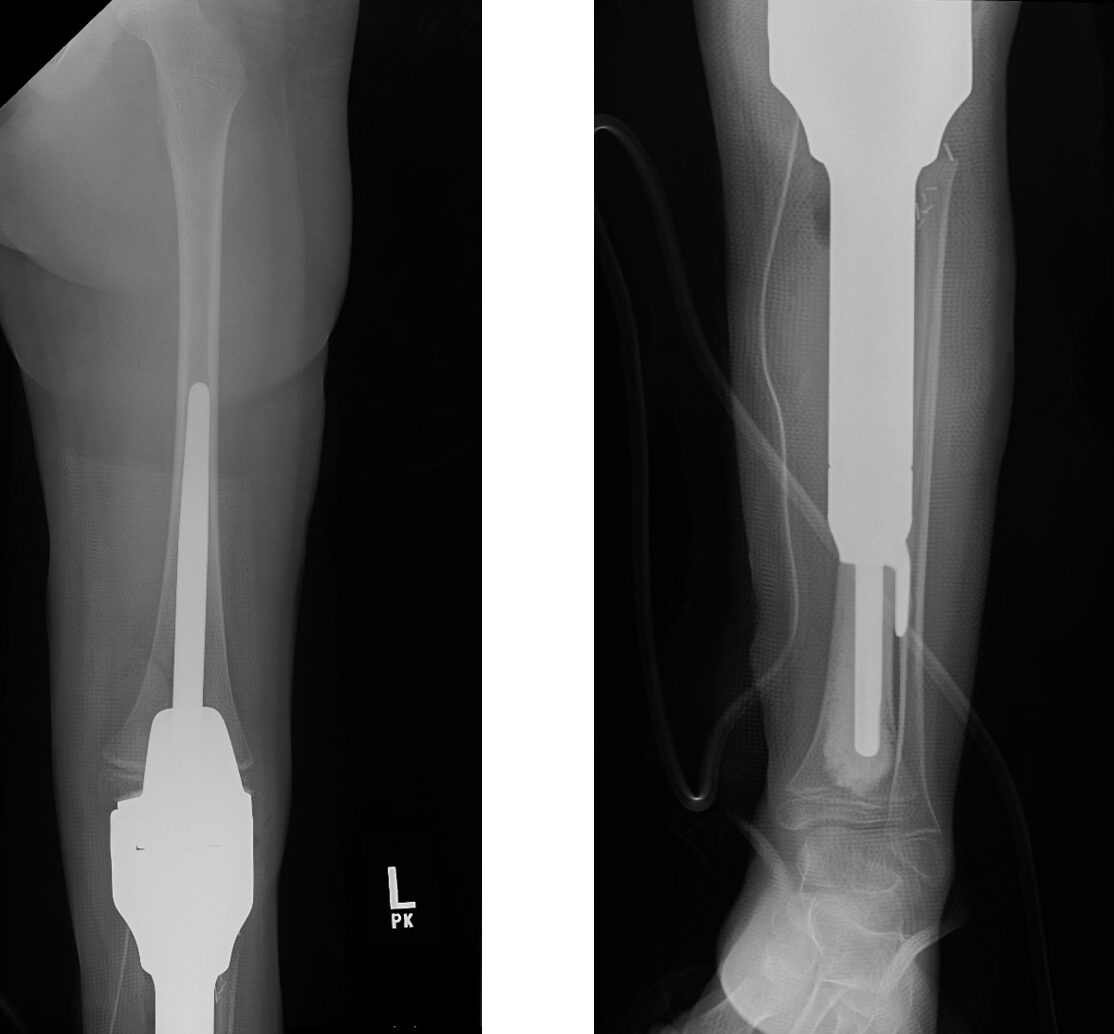

Proximal Tibia X-ray

This is an x-ray image of the tibial prosthesis post-surgically.

Intra-Op: Prosthesis Inserted

The prosthesis is inserted to match the length of the diseased bone removed and the prosthesis joint is attached to the upper femur bone.